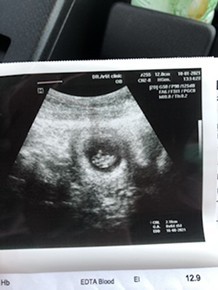

ตั้งครรภ์ 6 week ไม่เจอตัวอ่อน ใครเคยเจอบ้างคะ

วันนี้ไป u/s ทางช่องคลอดมาค่ะ เจอถุงตั้งครรภ์ แต่ไม่เจอตัวอ่อน หมอบอกว่า ท้องลม แนะนำให้ยุติการตั้งครรภ์ แต่ขอหมอไว้ก่อน อีก 1 อาทิตย์ ไม่มีแพ้ท้อง ไม่มีเลือดออก u/s ครั้งหน้ามีโอกาสจะเจอมั้ยคะ ตอนนี้กังวลมากค่ะ#ท้องแรกคะ #ขอบคุณล่วงหน้านะคะ #ใครมีประสบการณ์

อ่านเพิ่มเติมเหมือนกันเลยค่ะครั้งแรกที่ซาวก็ไม่เจอหมอบอกว่ามีแค่มดลูกตึงๆแต่ผลฉี่ก็บอกว่าตั้งครรภ์หมอเลยบอกว่าอายุครรภ์ยังน้อยอยู่รอมารอบหน้าต้องเจอถุงตั้งครรภ์เราก็ตกใจตลอดเครียดด้วยกลัวท้องลมแต่พอถึงนัดตอน8วิคก็เจอถุงตั้งครรภ์เจอตัวอ่อนจนตอนนี้24วิคแล้วค่ะใจเย็นๆนะค่ะรอดูก่อนค่ะ(อันนี้ภาพตอน8วิค)

ซาวตอน6wเจอแต่ถุงตั้งครรภ์เหมือนกันค่ะ เจอน้องตอน7wกว่าๆเล็กๆเอง แต่ตอนเจอแต่ถุงคุณหมอก็ยังไม่บอกนะคะว่าท้องลมคุณหมอบอกว่าถ้า10wแล้วยังไม่เจอเด็กถึงจะบอกค่ะว่าท้องลม สู้ๆนะคะของเราแท้งคุกคาม3รอบแต่น้องยังอยู่ ตอนนี้ต้องระวังตัวนอนเฉยๆได้หลายเดือนแล้วค่ะ สู้ๆนะคะ

ทำไมคุณหมอรีบบอกว่าเป็นท้องลมจังคะ ของเราu/sครั้งแรกทางช่องคลอดตอน 6w เจอแต่ถุงตั้งครรภ์ หมอเลยให้รออีก2อาทิตย์ว่ามีเด็กมั้ยแล้วค่อยฝาก แต่อีกหนึ่งอาทิตย์เราเปลี่ยนไปฝากที่คลินิกอีกที่เค้าu/sทางท้องให้ ก็เจอเด็กและหัวใจเต้นแล้วค่ะ

บ้านนี้ซาวด์ผ่านหน้าท้อง ต้อน 6w6d ก็ยังไม่เจอตัวอ่อนค่ะเจอแต่ถุงการตั้งครรภ์และไข่แดงในถุงตั้งครรภ์ หมอนัดดูอีกที 3 สัปดาห์ หมอบอกจะเจอน้องประมาณ 8 วีคค่ะแม่